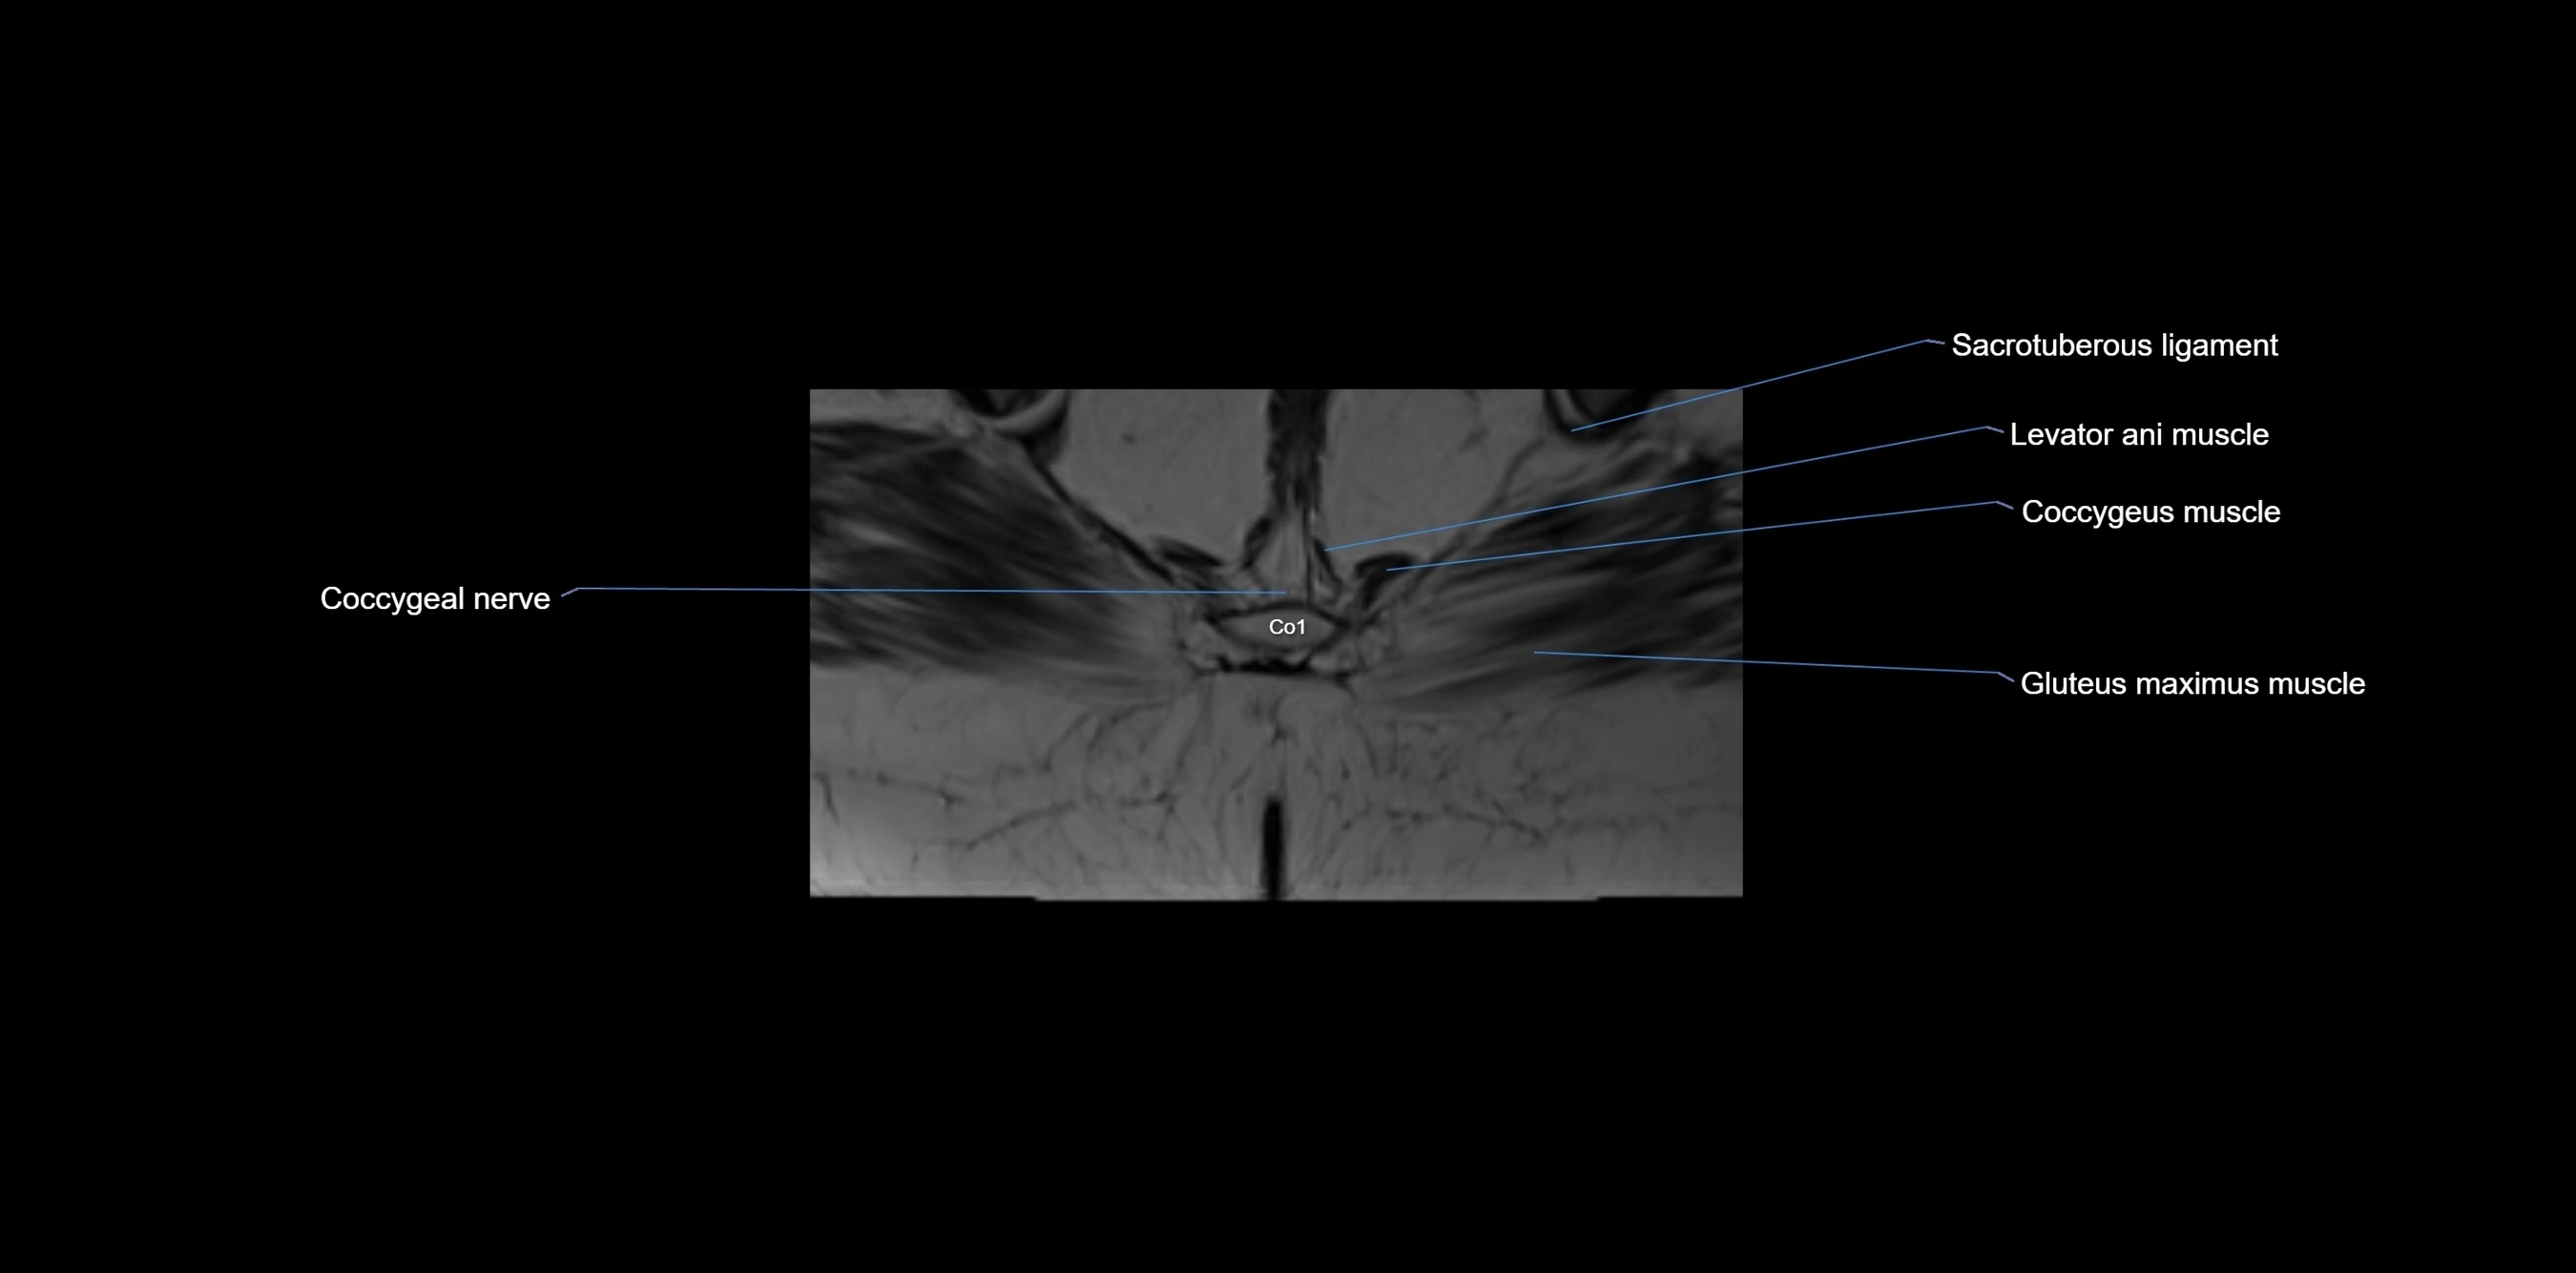

CT VRT image

image